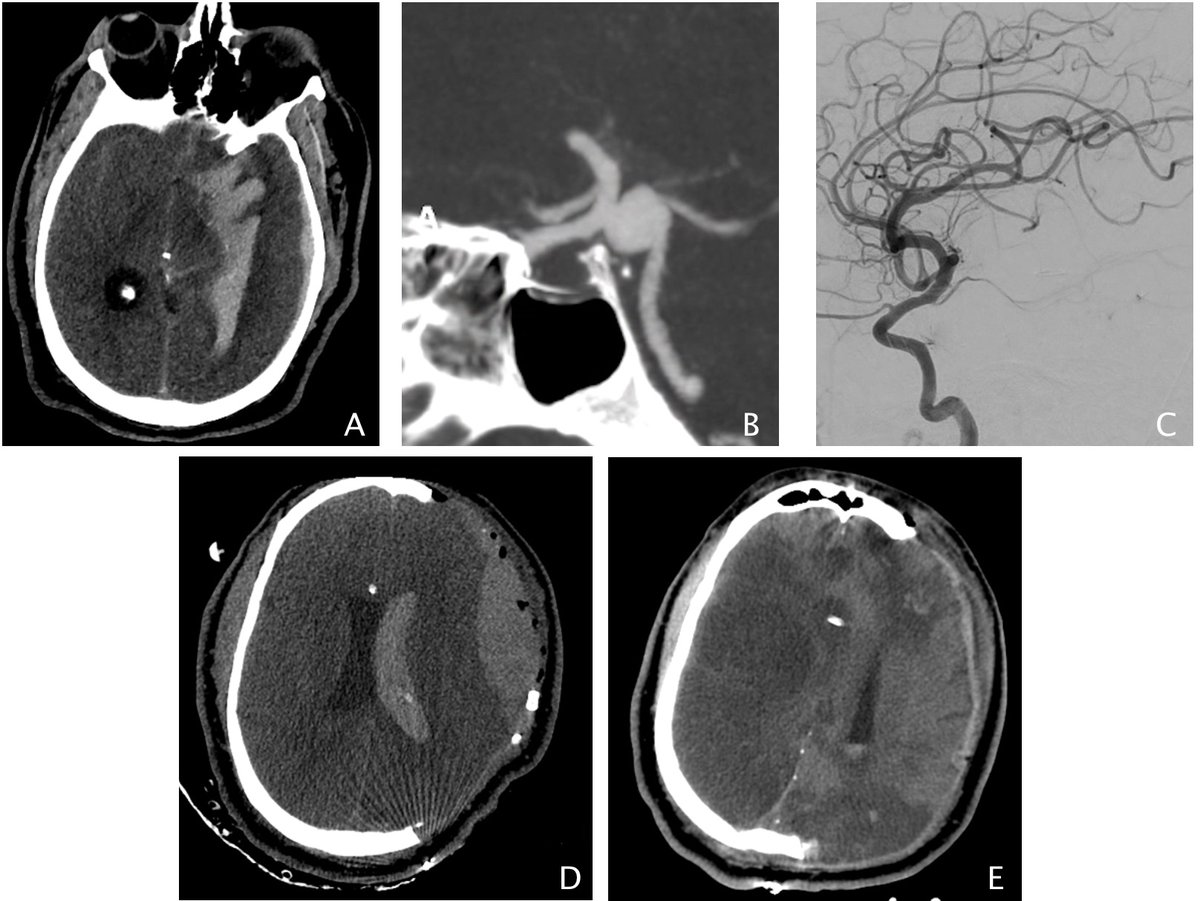

Today’s thrombectomy shows the role of direct manual aspiration through balloon guide catheter for carotid large clot burden. #stroke #largeclot #thrombectomy